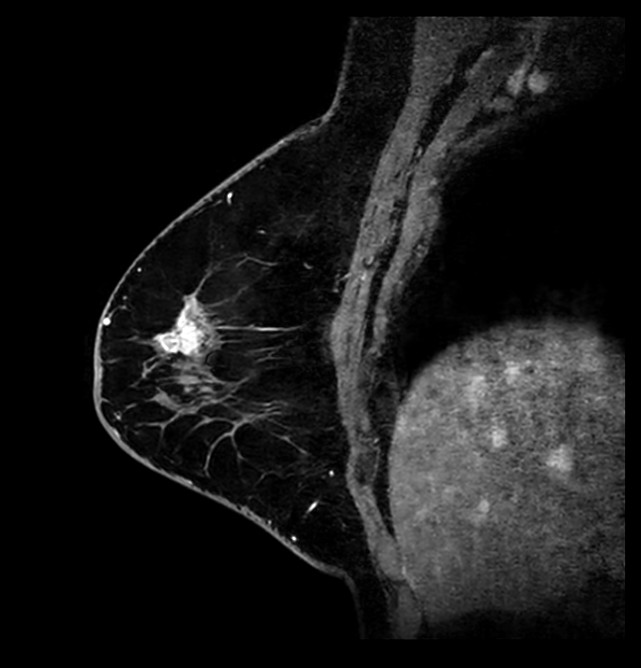

Sagittal 3D mDIXON gado (MPR)